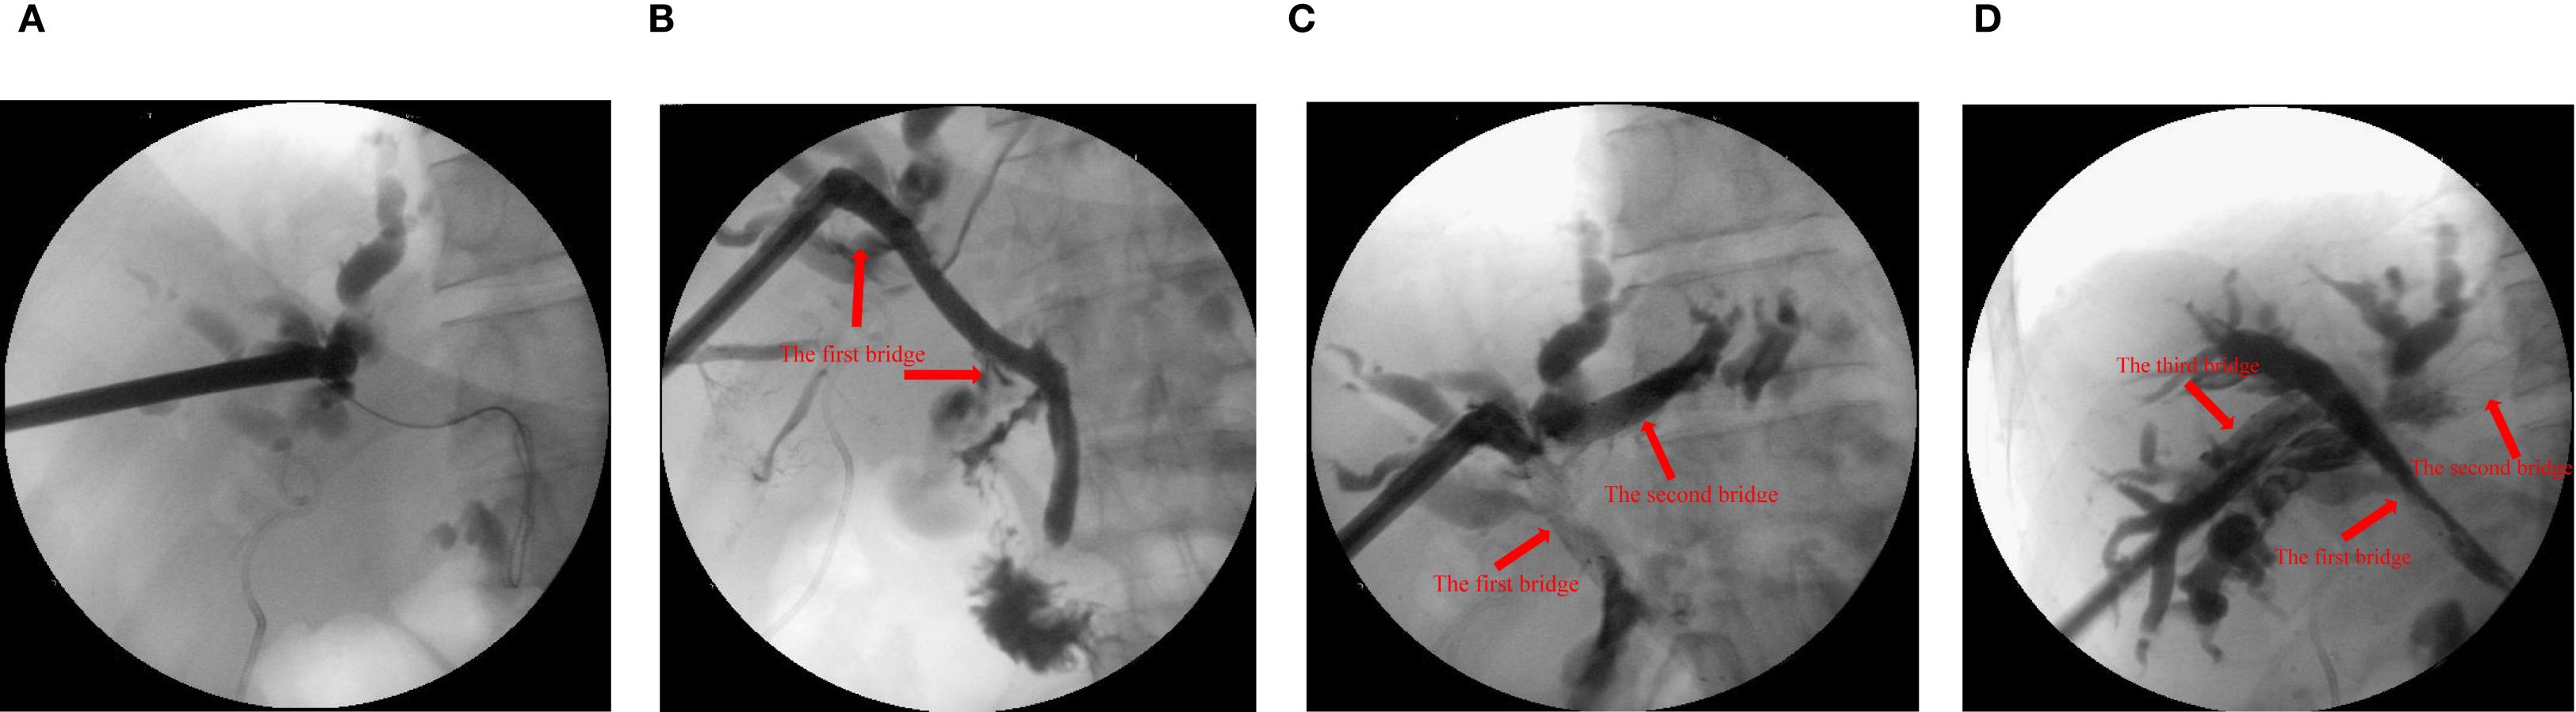

Step 2: Choledochoscopy revealed distal obstruction of the right anterior hepatic duct, preventing guidewire passage. Then, a puncture needle was used to puncture the right anterior hepatic duct to the distal common bile duct, and a balloon was used to dilate the channel. A self-expanding metal stent was deployed, creating the first bridge. Intraoperative cholangiography confirmed successful bridging between the right anterior hepatic duct and the distal common bile duct (the first bridge).

Step 3: Under combined PTCS and ultrasound guidance, the right anterior hepatic duct was punctured into the left hepatic duct. The tract was re-dilated, and an 8 x 60 mm metal biliary stent was deployed, forming the second bridge. X-ray examination by injecting contrast agent showed successful bridging of the right anterior and left hepatic ducts (the second bridge), but poor imaging of the right posterior hepatic duct suggested that the right posterior hepatic duct may still be narrow.

Step 4: Finally, ultrasound-guided puncture from right anterior hepatic duct into right posterior hepatic duct. The passage between the right anterior and right posterior hepatic ducts was re-dilated using the guidewire. The right anterior hepatic duct was bridged with an 8 x 60 mm metal biliary stent to the right posterior hepatic duct. Cholangiography confirmed successful communication between the right anterior and right posterior hepatic ducts (the third bridge) (Figure 1).

Figure 1. X-ray examination with contrast agent injected through the sinus. (A) the common bile duct before guide wire puncture and balloon dilation. (B) the right anterior intrahepatic bile duct and the common bile duct were bridged with metal stent (10x60 mm, the first bridge). (C) the left and right anterior intrahepatic bile ducts were bridged with metal stent (8x60 mm, the second bridge). (D) the right anterior and right posterior intrahepatic bile ducts were bridged with metal stent (8x60 mm, the third bridge).